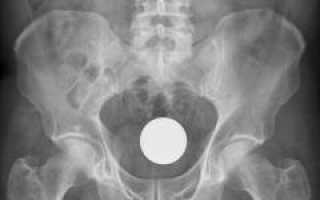

| Ультразвуковая диагностика (УЗИ). | Исследование органов малого таза, включая матку, трубы, яичники и мочевой пузырь. Часто включает трансвагинальное исследование с использованием специального датчика. | Помогает различить вульвовагинит и воспалительные процессы в матке и её придатках (аднексит), а также выявить опухоли на ранних стадиях. |